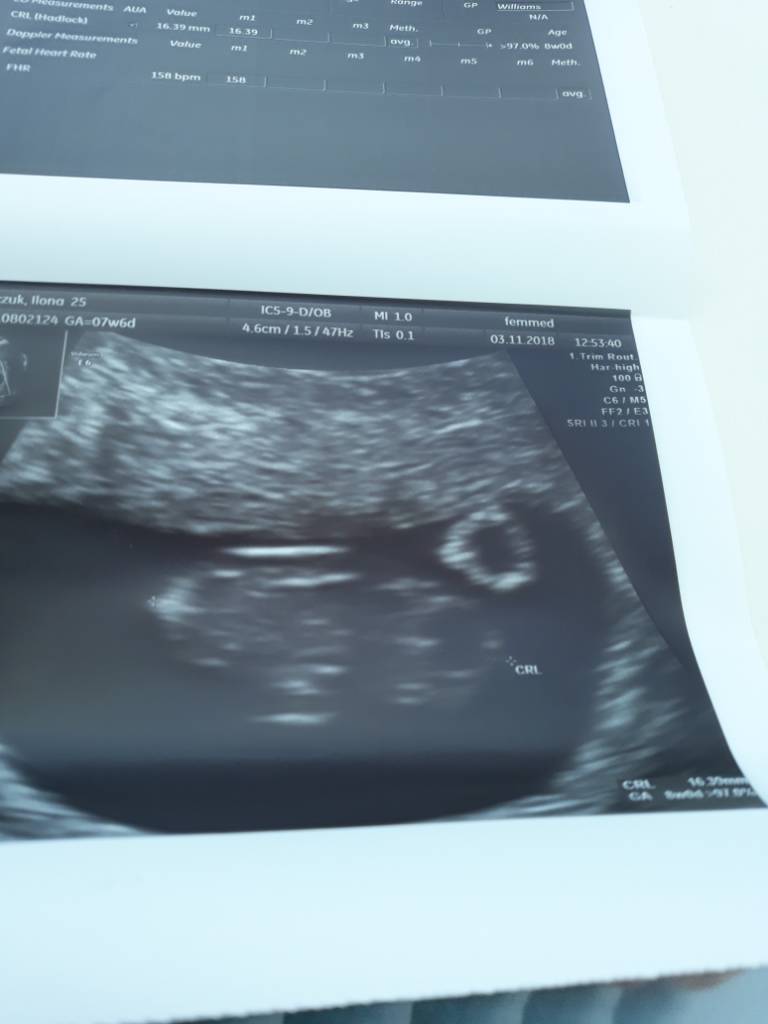

Chciałam do was dołączyć powiedzieć że mi też w końcu się udało, owulacja w 39dc dopiero 10 dpo pozytywny test, w 11dpo beta 35 a w 13 już 108.

Pierwsza wizyta 18.01. Trzymajcie kciuki :)